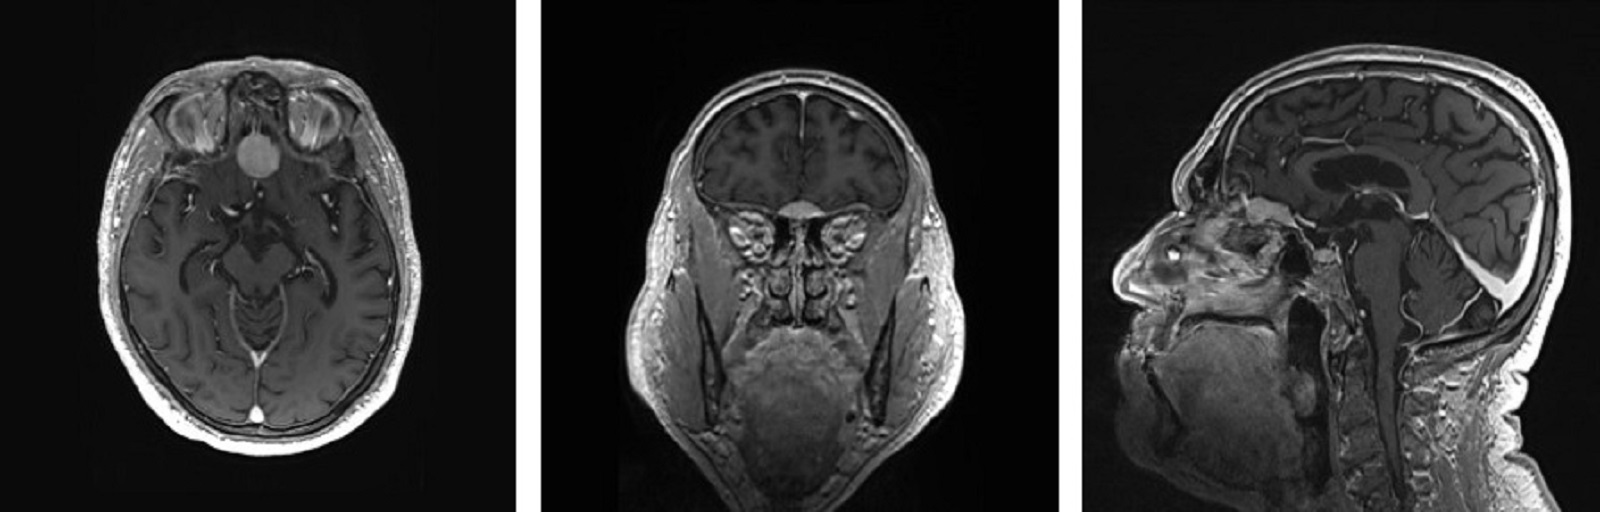

Hoygradige Gliomer Hos Voksne Tidsskrift For Den Norske Legeforening

Hoygradige Gliomer Hos Voksne Tidsskrift For Den Norske Legeforening from tidsskriftet.no